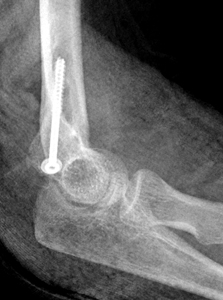

Medial_epicondyle_Figure2B_1151248_1_Medial_epo_AP2_ORIF.jpg  Medial_epicondyle_Figure2B_1151248_2_Latera_ORIF.jpg

B

Figure 2: A) Thirteen year old gymnast with medial epicondyle fracture. The medial epicondyle is separated >5 mm (red arrow). This is evident on the AP view. It is more difficult to see on the lateral view due to the splint. B) Due to the child's age and type of sporting activity, management was open reduction and internal fixation.